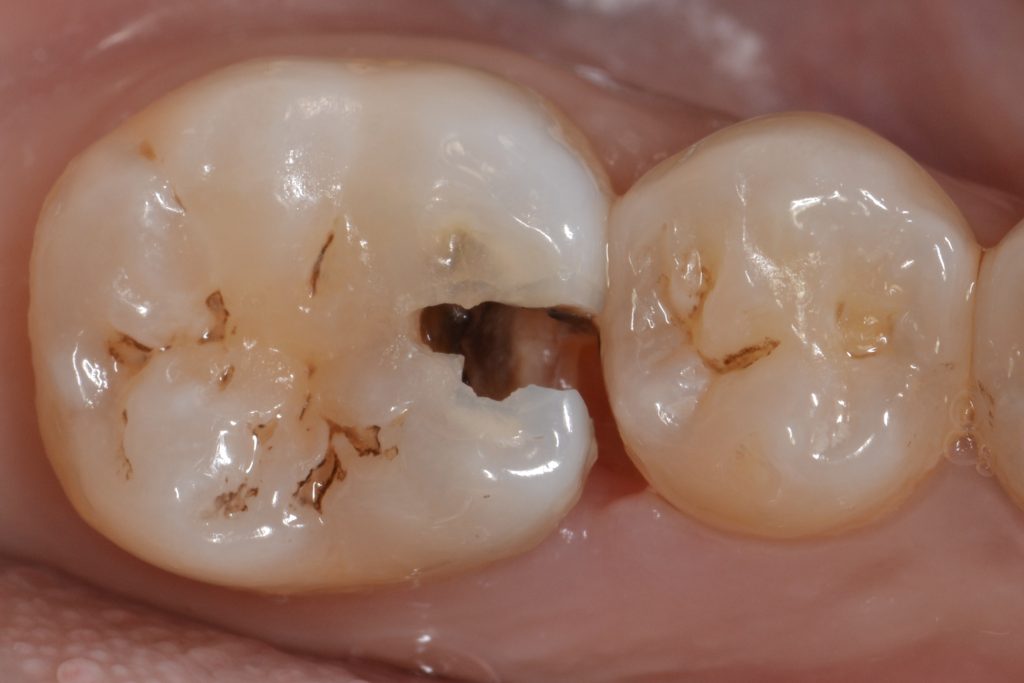

The patient presented to the clinic with a chief complaint of sensitivity and food impaction in the lower right quadrant, the clinical examination showed a large decay in the first lower molar.

The treatment plan involved removing the caries, building the proximal wall with composite, then using fibre reinforced composite as a dentin replacement (reinforce the composite restoration in large size cavities), finally restoring the cusps with composite.